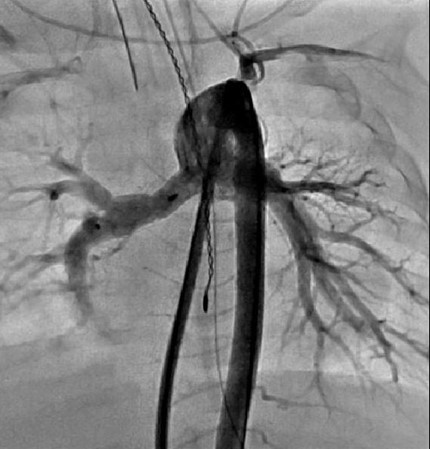

Figure 2

Figure 2. Angiographic evaluation of flow restrictors two weeks following placement. The PFR in the RPA jails the right upper pulmonary artery (RUPA), however this image demonstrates continued flow into the RUPA.